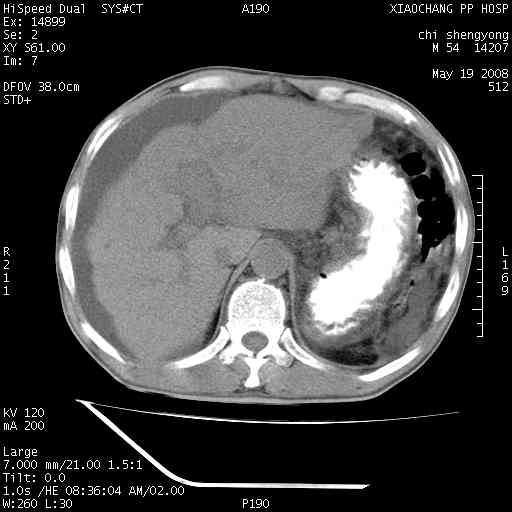

以下是引用zjzjr在2008-5-21 10:52:00的发言:[br]肝左叶巨块型肝癌伴门静脉左支瘤栓形成.肝硬化、腹水,胃底静脉曲张,脾术后改变。

以下是引用随光逐影在2008-5-21 16:20:00的发言:[br]1)肝左叶肝癌伴门静脉左支瘤栓形成,腹膜后淋巴结转移。2)肝硬化、腹水、胃底静脉曲张。3)胆囊炎。4)脾脏缺如,为切除术后所致。